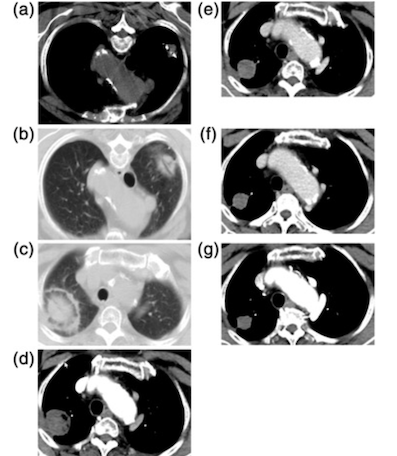

CT of an 80-year-old woman with right upper lobe adenocarcinoma at stage IA (cTlaNOMO). (a) The MWA antenna is shown centrally positioned within the tumor [8]. (b) Ground-glass opacity around the tumor and cavity ni the core was observed ni the image obtained immediately postablation. (c) The axial CT with lung window showed expected thermal damage around the target lesion, without pneumothorax, 24 hours postablation. (d) The enhanced CT image at one month after MWA; the size of the ablation zone was larger than the target tumor but was not enhanced. (e-g) The images at six, 12, and 91 months after MWA; the ablation zone shrank continuously and remained nonenhanced.